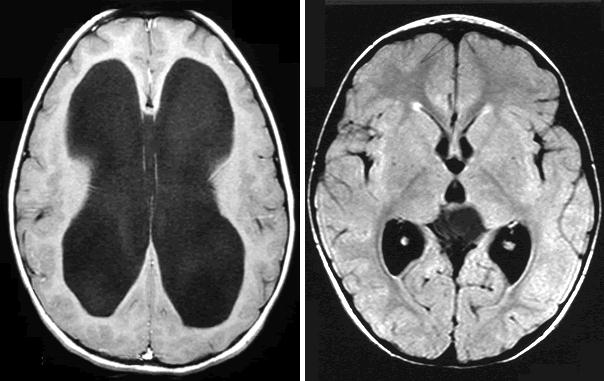

КТ-признаком СГЦФ является увеличение всех желудочков, включая IV. Для окклюзионной ГЦФ более характерна тривентрикулярная ГЦФ (расширение боковых и III желудочков при нормальных размерах IV желудочка) .

На левом слайде представлен пример внутренней гидроцефалии, на правом регресс гидроцефалии после проведенного шунтирования.